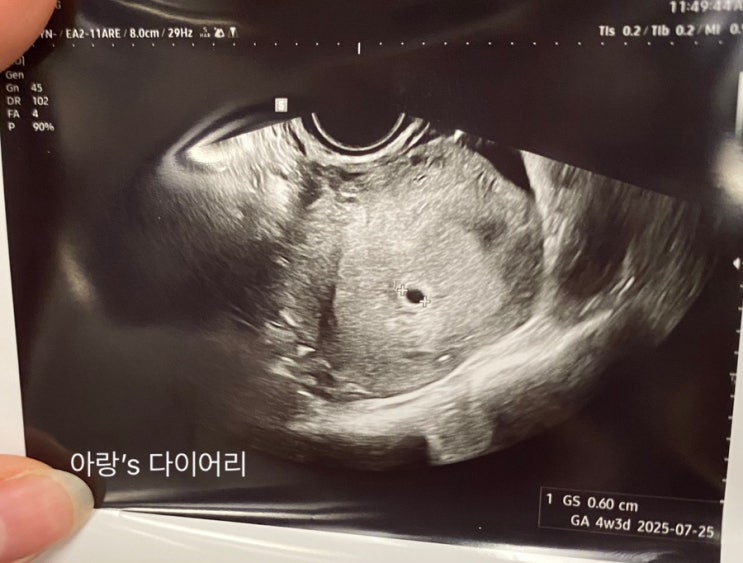

둘째일기 네번째 임신초기 아랫배 통증으로 병원 내원

이번 임신은 시작부터 배가 아팠던적이 종종 있었는데 첫 아기집을 보고 4일이 지난 후였던 금요일 아랑이...